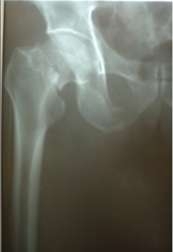

二、现代手术治疗